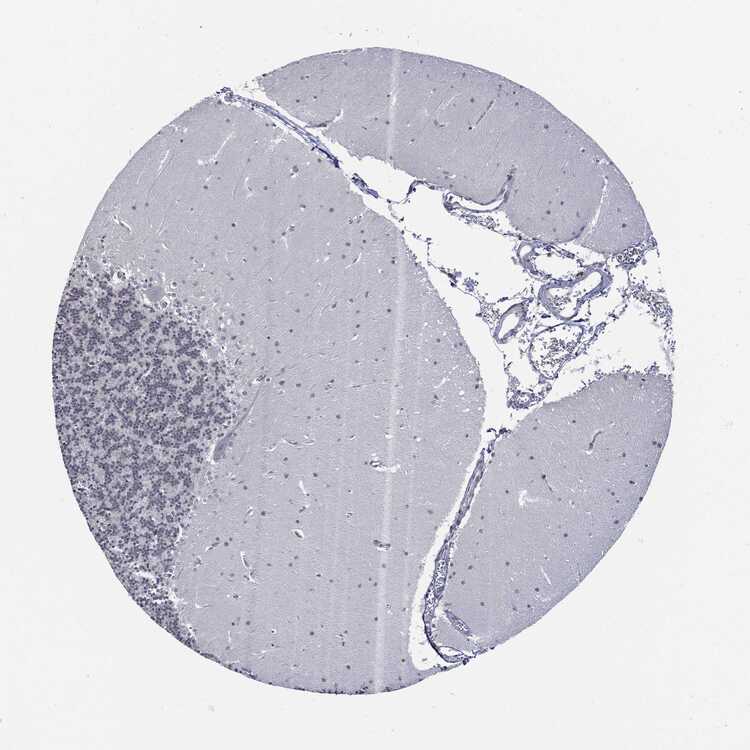

CEREBELLUM - Antibody stainingi

Antibody staining in the annotated cell types in the current human tissue is reported as not detected, low, medium, or high, based on conventional immunohistochemistry profiling in selected tissues. This score is based on the combination of the staining intensity and fraction of stained cells.

Each image is clickable and will lead to virtual microscopy that enables deeper exploration of all samples and also displays staining intensity scores, fraction scores and subcellular localization as well as patient and tissue information for each sample.

Antibody HPA030521Antibody HPA030522Antibody HPA030523Antibody CAB000148Antibody CAB080240Antibody CAB080241Antibody CAB080242

Purkinje cells Not detectedNot detectedNot detectedNot detectedNot detectedLowNot detected

Cells in granular layer Not detectedNot detectedNot detectedLowNot detectedNot detectedLow

Cells in molecular layer Not detectedLowNot detectedLowNot detectedLowLow